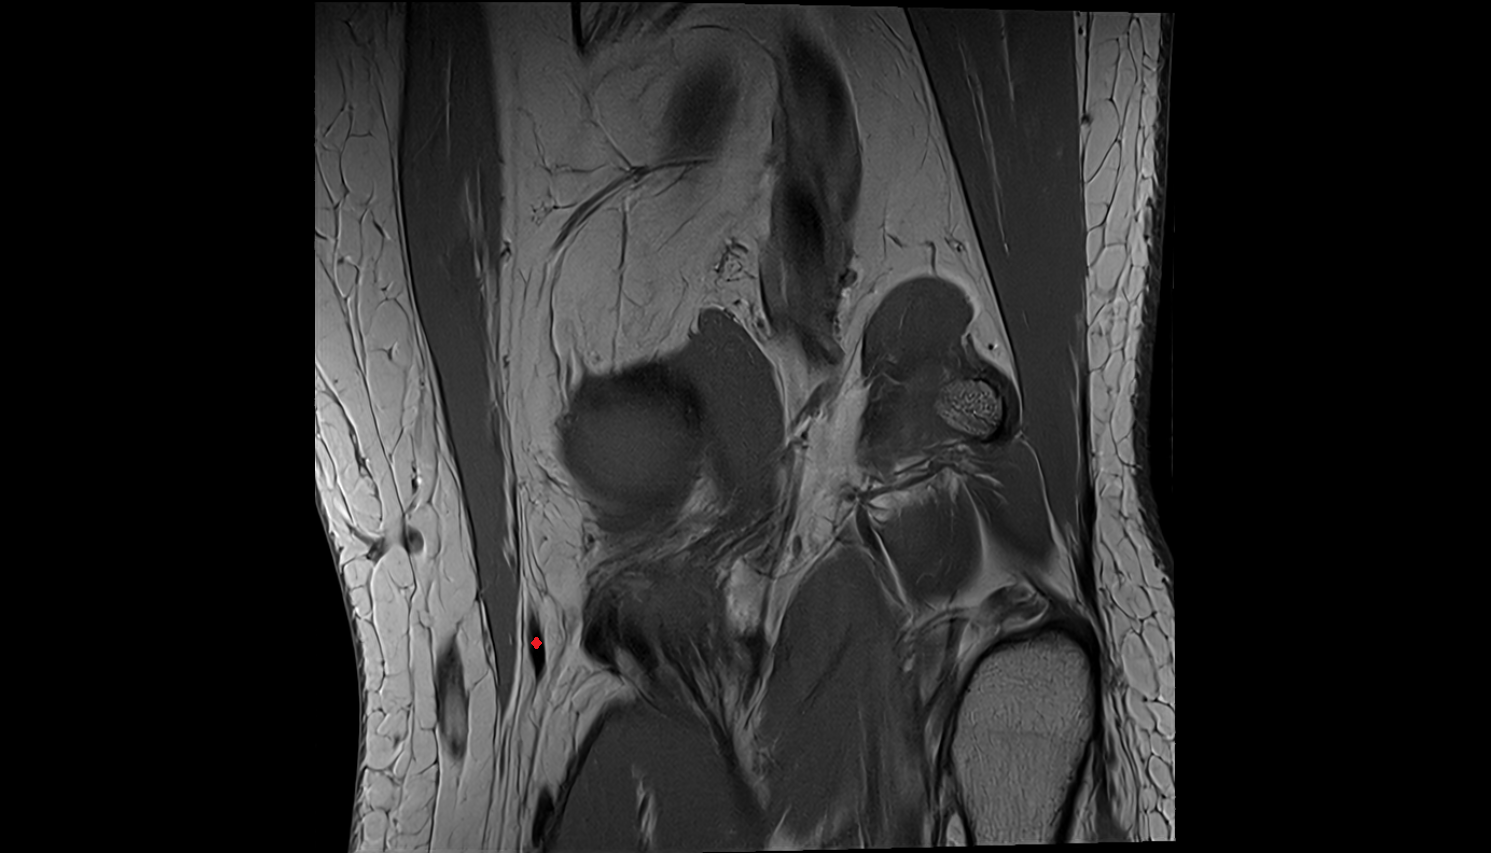

- Medial meniscus

- Lateral meniscus

- Anterior horn of medial meniscus

- Posterior horn of medial meniscus

- Body of medial meniscus

- Anterior horn of lateral meniscus

- Posterior horn of lateral meniscus

- Body of lateral meniscus